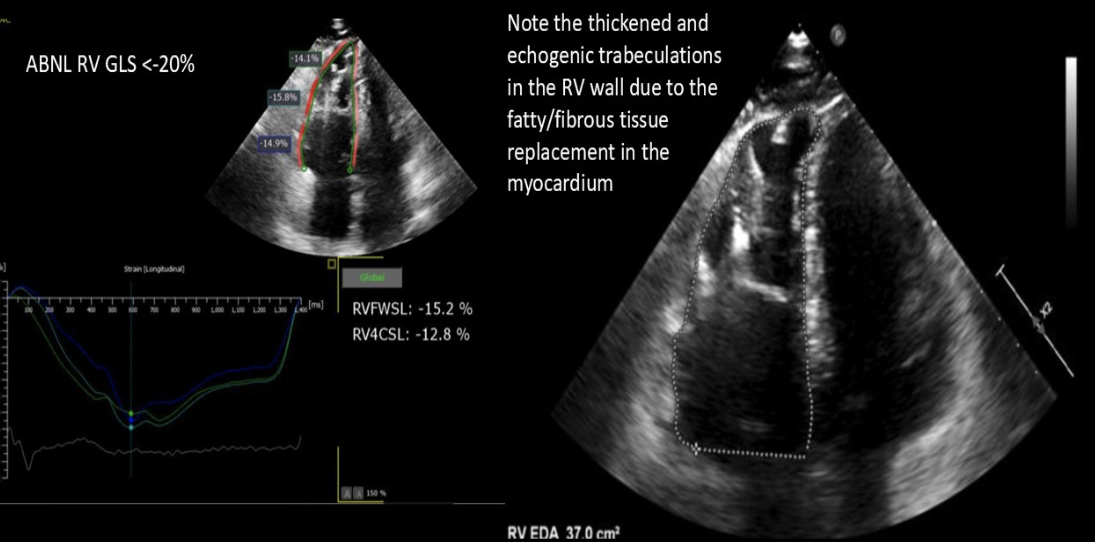

Fatty and fibrous tissue replacement of the myocardium of the RV

Arrhythmogenic RV cardiomyopathy